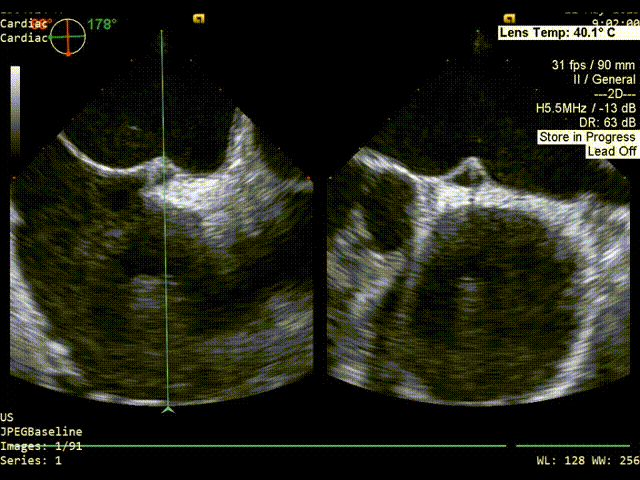

双房切面超声影像

静息状态下房水平见左向右分流。

隧道长度14mm(双房切面);

2、PFO参数:隧道裂隙宽约2mm;卵圆孔隧道长度8.2mm(主动脉短轴)14.6mm(双房切面)。